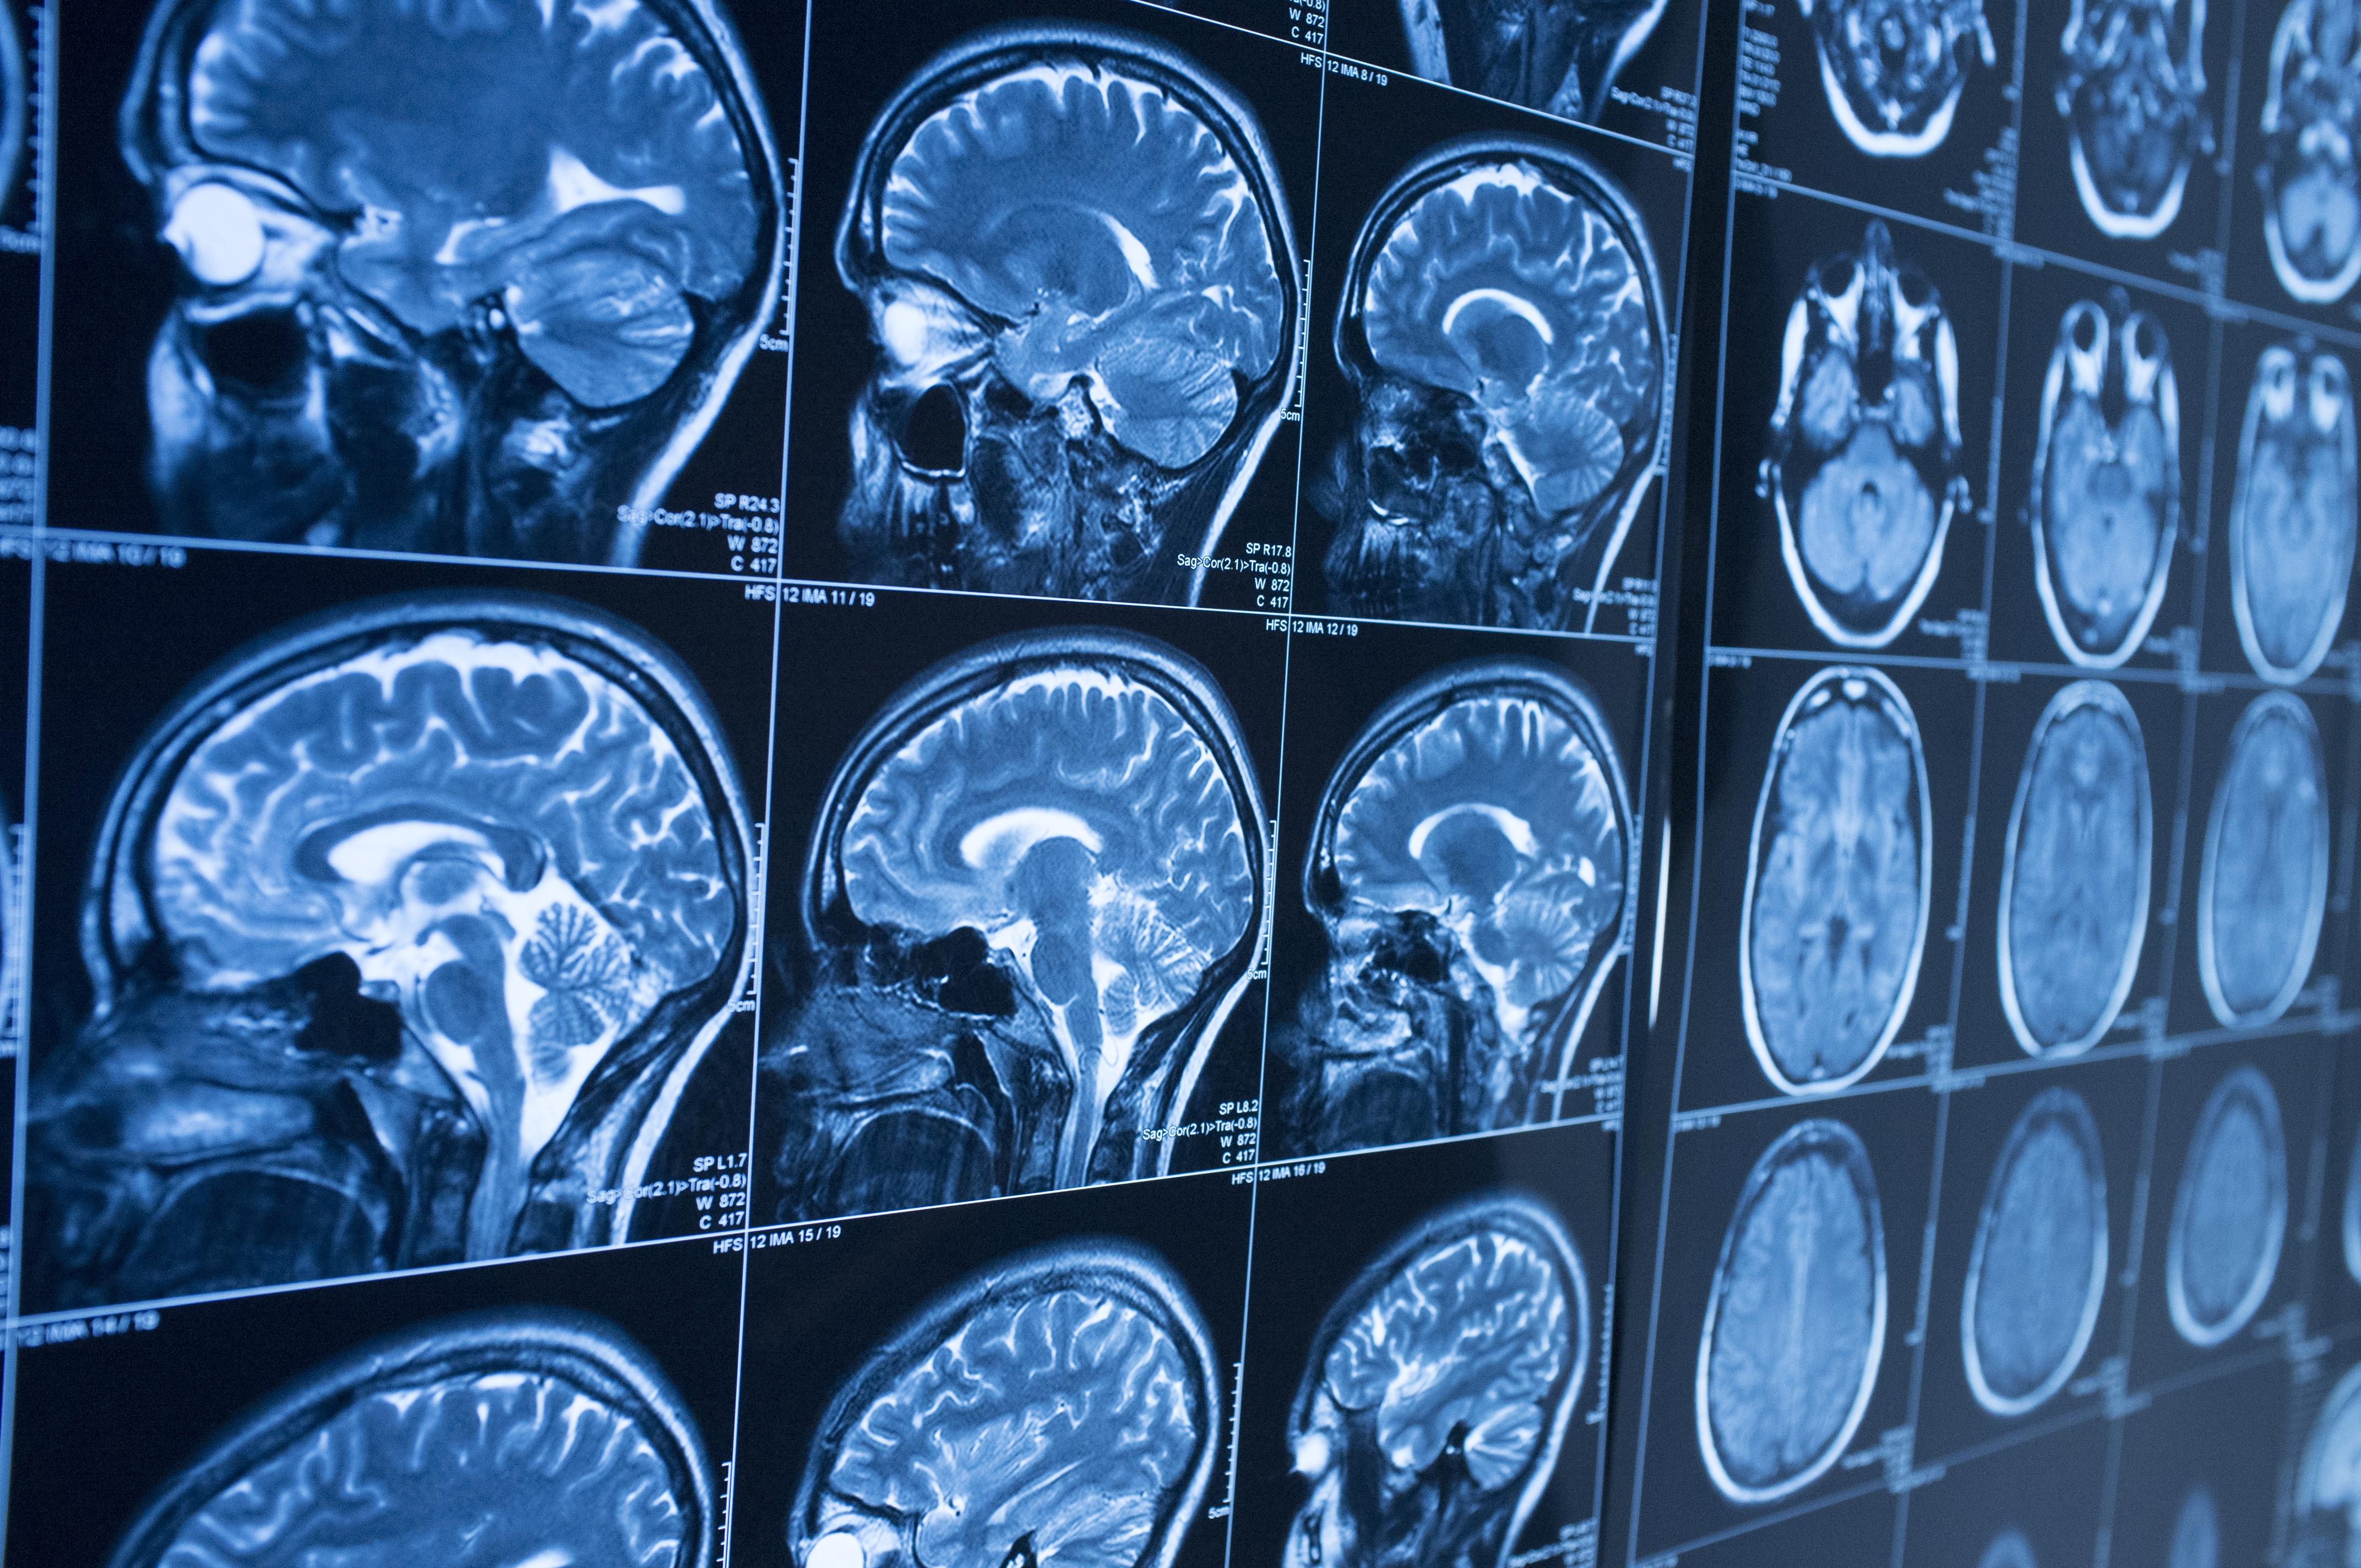

Des cellules souches imprimées en 3D pour traiter les blessures cérébrales

Une nouvelle avancée de la science pourrait bien marquer un progrès majeur pour la médecine. En effet, des chercheurs de l’Université d’Oxford viennent d’imprimer en 3D des cellules souches capables de répliquer l’architecture du cortex cérébral. Il s’agit de la couche externe du cerveau, aussi cette technique pourrait servir à traiter des blessures cérébrales impactant le mouvement, la communication, ou plus généralement les processus cognitifs. Il n’existe aujourd’hui aucun véritablement traitement pour les blessures sévères de ce type, aussi les espoirs sont grands quant à cette découverte.

Pour ce faire, les chercheurs ont utilisé des cellules souches pluripotentes, dérivées de cellules prélevées directement sur les patients. Ce qui réduit considérablement les risques de réponse immune. Ils ont ensuite séparé ces cellules en types de cellules neuronales progénitrices correspondant à deux couches du cortex cérébral. Après quoi, ils les ont plongées dans une solution spécifique qui a mené à deux « bio-encres », imprimées pour reproduire la structure du tissu cérébral. Et d’après les premiers tests sur des souris, l’intégration structurelle comme fonctionnelle est un succès.

La prochaine étape pour les scientifiques ? Faire évoluer cette technique pour créer du tissu cérébral complexe à plusieurs couches, afin de pouvoir s’attaquer au cerveau humain et son architecture particulière de façon plus réaliste.